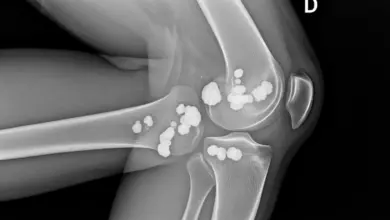

A ressonância magnética é o exame que melhor mostra a profundidade da lesão condral, sua localização e possíveis alterações associadas.

Ela ajuda a entender se existe comprometimento mais focal, desgaste mais amplo ou envolvimento de outras estruturas do joelho.